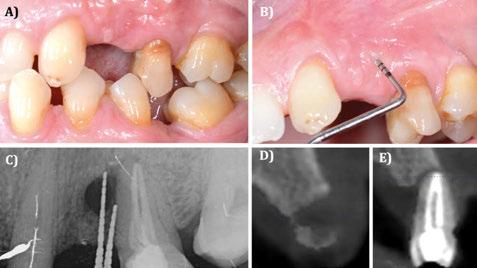

Figura 9. Caso clínico con membrana reabsorbible.

A) Situación clínica basal. B) Sondaje a través de la fístula en basal. C) Situación radiográfica basal (2D). D) Situación radiográfica basal en posición de 24 (3D). E) Situación radiográfica basal en posición de 25 (3D).